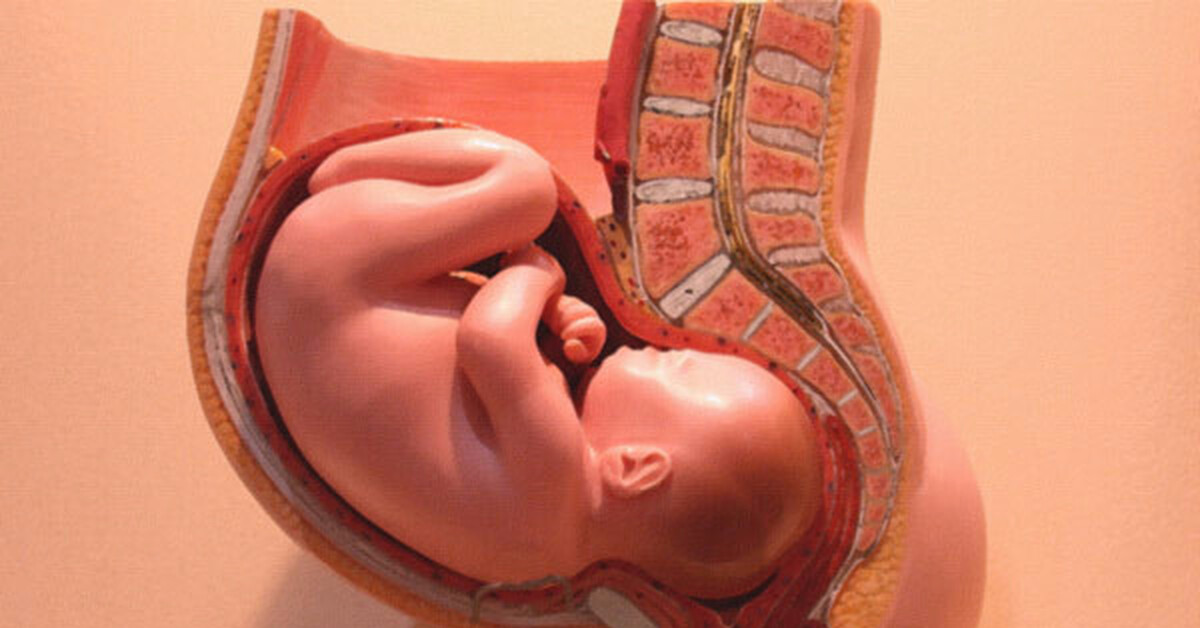

Плод 39 Недель Фото

Плод 39 Недель Фото 100 фото